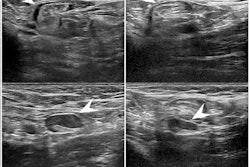

The median maximal cortical thickness on initial ultrasound was found to be 5 mm in women who were recommended biopsy, compared with 4 mm for women who weren't recommended.

Three patients were diagnosed with malignant axillary adenopathy. Biopsy was recommended for all three from 12 to 13.1 weeks after the second vaccine dose. They also had a maximal cortical thickness of at least 5 mm and "highly suspicious" sonographic features, the researchers said.

The opposite could be said for all 29 women who had benign biopsy. They had symmetric cortical thickening and no suspicious sonographic features.